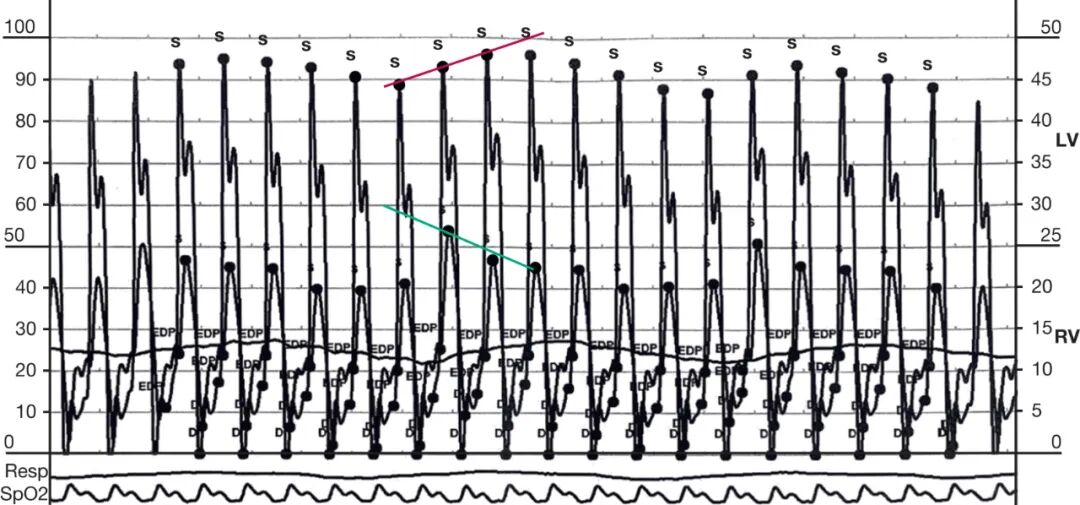

左右心功能同步检查显示心室呼吸相依赖性伴压力变化不一致,舒张末期压力均衡,以及早期舒张心室压力下降后迅速上升并呈平台期(图2)。

CP患者在体格检查上的典型特征包括:由于快速心室舒张突然停止所致的高调舒张期杂音(即心包叩击音),吸气时颈静脉压不下降(即库斯莫尔征),以及吸气时收缩压下降加剧(即奇脉加重)。心室压力追踪图的特点是心室不同步(图 2);下降-平台形态特征(即平方根征),这反映了心室舒张早期快速充盈随后因心包顺应性差而突然停止;以及舒张末期压力均衡。颈静脉波形的x和y降支(分别反映心房松弛和排空)显著突出(M征或W波形)(图 3)。这反映了心房压力升高和心房快速排空,有助于将CP与心脏压塞

2.在心导管检查中,心室不同步、平方根征、舒张末期压力均衡以及显著的x和y降支与CP相符。